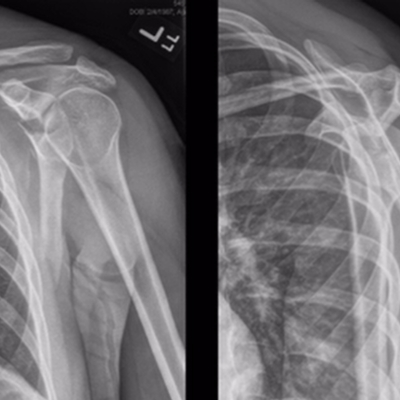

Click on an image below to view more info.